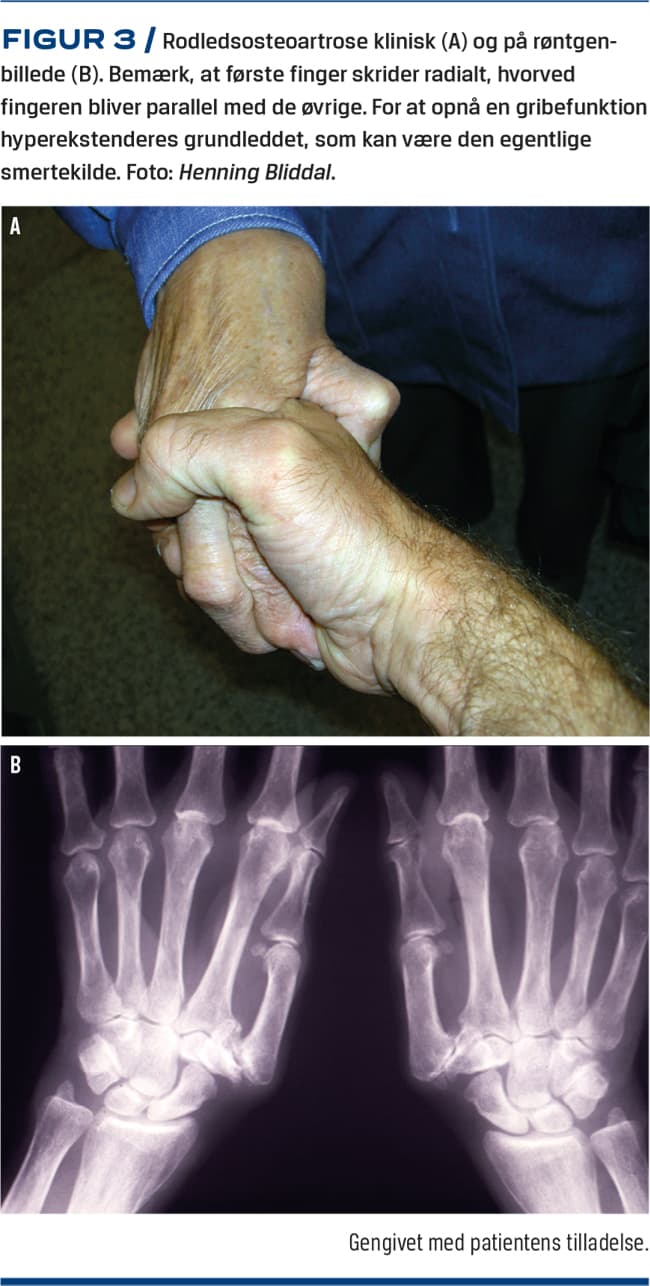

Rodledsartrose

Ved OA i karpometakarpalled et displaceres leddet, hvorved første finger bliver mere parallel med de øvrige (Figur 3). For at bevare en gribefunktion vil grundleddet ofte blive hyperekstenderet, og smerten ved grebet kan stamme fra både rod- og grundleddet. Dette problem kan ikke trænes væk, og operation for rodleds-OA kan slå fejl, hvis problemet i virkeligheden stammer fra grundleddet. Situationen kan søges bedret ergonomisk, ved at patienten holder genstande helt inde i »gaflen« frem for at bruge pincetgreb.